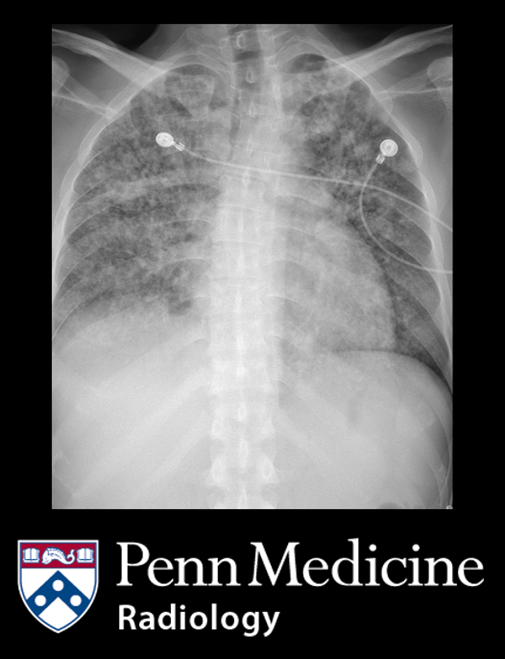

59-year-old man with hypoxic respiratory failure

A 59-year-old man with a past medical history of progressive fibrotic lung disease developed hypoxic respiratory failure secondary to an interstitial …